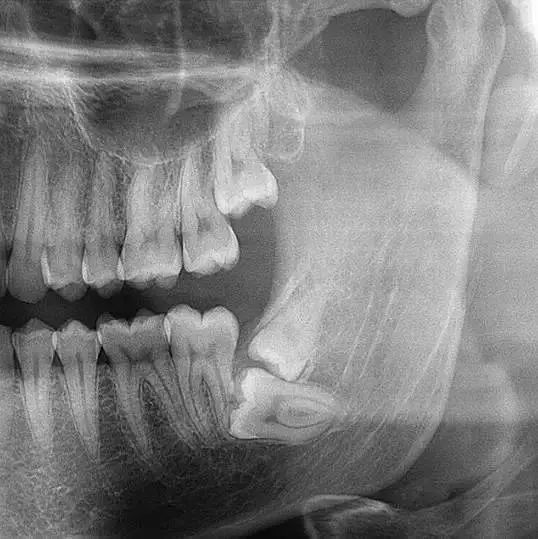

先放几张图,让你们涨涨姿势,不拍片根本不知道你的牙齿长得会有多奇葩!

牙齿的牙根是埋在牙槽骨中的,医生没有透视眼,为了解患牙的牙根的形态、走向、长度及根尖周有无病变及病变大小,或者怀疑有肉眼无法确认的其它牙科问题,都会建议患者去牙科的X光,甚至,口腔CT来全面性地确认问题,以订定合适的治疗计划。